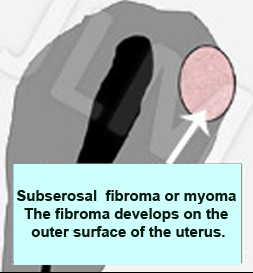

When fibromas grow on the outside of the uterus they are termed subserosal fibromas. Unless they are very large, these rarely cause any symptoms. In terms of size, large fibromas can measure several tens of centimeters resembling a melon or bigger. In these cases such fibromas can compromise the bladder, the urethras, and leave the patient with the feeling of wanting to pass urine to the extent that the kidneys may even dilate. There may also be difficulties in giving birth when the baby is sitting low (Praevia).

When fibromas grow on the outside of the uterus they are termed subserosal fibromas. Unless they are very large, these rarely cause any symptoms. In terms of size, large fibromas can measure several tens of centimeters resembling a melon or bigger. In these cases such fibromas can compromise the bladder, the urethras, and leave the patient with the feeling of wanting to pass urine to the extent that the kidneys may even dilate. There may also be difficulties in giving birth when the baby is sitting low (Praevia).